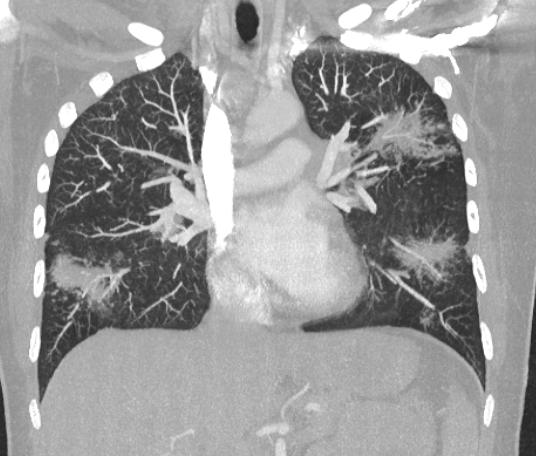

冠状位重建HRCT示多个结节影被多个淋巴分布的微小结节包围,呈现“星系征”外观。

冠状面 MIP 重建示“星系征”。